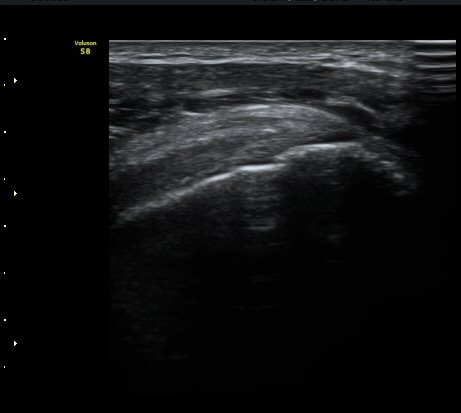

±Ø»ó°Ç ±ÙÀ§ºÎ Ⱦ´Ü¸é°Ë»ç¿¡¼­ Á¡¾×³¶ÀÇ °æ¹ÌÇÑ ºÎÁ¾ ¿Ü¿¡ ƯÀÌ ¼Ò°ßÀ» º¸ÀÌÁö ¾ÊÀ½(±×¸² 6).

±Ø»ó°Ç ¿øÀ§ºÎ Ⱦ´Ü¸é°Ë»ç¿¡¼­ ´ë°áÀý°ú »ó¿Ï°ñµÎ ÀÌÇàºÎÀ§¿¡ ÇÇÁú°ñ ¿¬¼Ó¼º ¼Ò½ÇÀ» º¸ÀÓ(±×¸² 7).